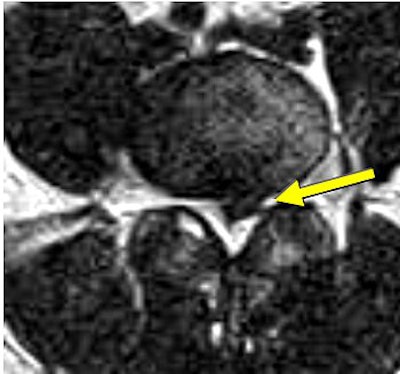

| Same patient as above. Top, transaxial T2-weighted image showed left L4 spinal nerve root compromise with axial loading (below). |